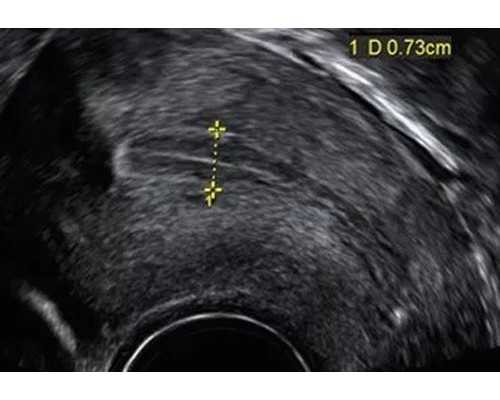

4. 改善子宫内膜厚度: 维生素E可以促进子宫内膜的血液循环,增加子宫内膜的厚度,提高着床的成功率。子宫内膜是受精卵着床的地方,厚度的增加可以为受精卵的生长提供更好的环境。